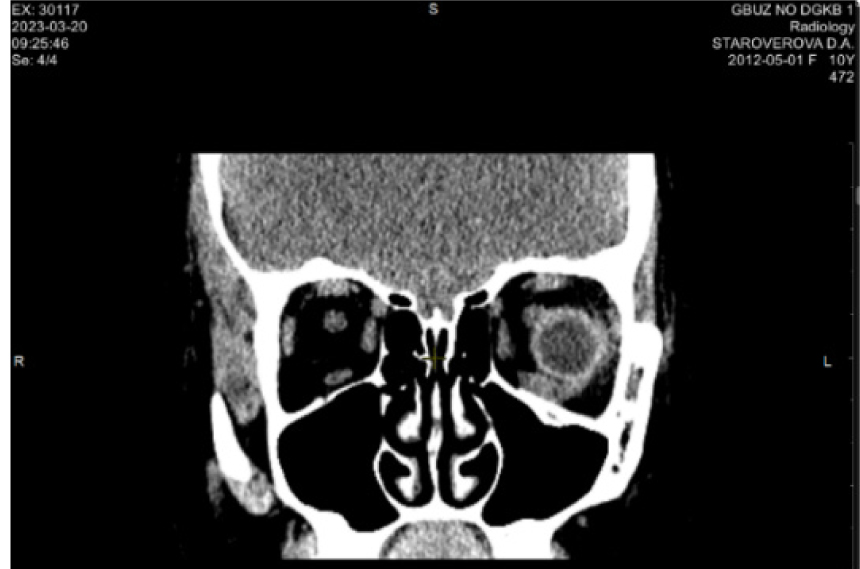

По результатам КТ и данным анамнеза на этапе планирования операции предположили отсутствие нижней прямой мышцы справа (рис. 6).

Пациентке поставлен диагноз: Оперированная травматическая деформация орбиты. Травматическое косоглазие. Рекомендовано хирургическое устранение косоглазия. С этой целью проведена нижняя парциальная транспозиция боковых прямых мышц в следующем объеме: от внутренней и наружной прямых мышц отделены порции в 2/5 ширины сухожилия, перемещены книзу и фиксированы в месте крепления нижней прямой мышцы. Также выполнена рецессия верхней прямой мышцы 3 мм. В раннем послеоперационном периоде отмечено уменьшение вертикальной девиации и появление подвижности книзу (рис. 7).

Рис. 6. Компьютерная томография орбит до операции. Клинический пример 2